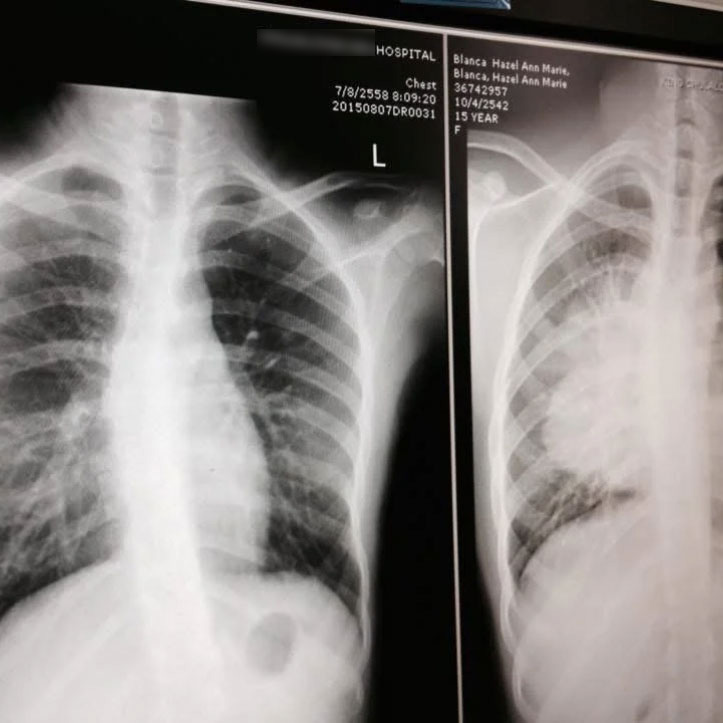

อายุเพียง 15 ปี เธอถูกวินิจฉัยว่าเป็น มะเร็งต่อมน้ำเหลืองชนิดนอนฮอดจ์กิน ระยะที่ 4 มะเร็งที่เกิดในระบบน้ำเหลือง ส่วนหนึ่งของระบบภูมิคุ้มกันของร่างกาย อาการเริ่มจากการไอนานหลายเดือน ก่อนจะไอเป็นเลือด และพบก้อนเนื้อขนาดใหญ่ที่คอและหน้าอก

เธอได้รับข่าวร้ายที่โรงพยาบาล โดยมะเร็งของเธอลุกลามไปถึงระหว่างหัวใจและปอด "ฉันจำได้ว่าตอนนั้นอยู่คนเดียวในห้องฉุกเฉิน โทรศัพท์ก็แบตหมด ฉันกลัวมาก" เธอเล่า "แต่แล้วแพทย์ฝึกหัดคนหนึ่งเดินเข้ามานั่งข้างๆ ยื่นโทรศัพท์ให้โทรหาแม่ รอยยิ้มของเขาทำให้ฉันสงบลงอย่างไม่น่าเชื่อ"